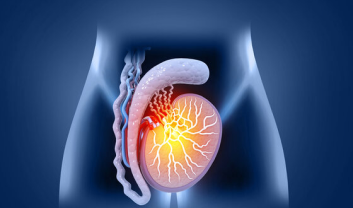

PUJO obstruction occurs when there is a blockage at the point where the kidney's pelvis connects to the ureter, hindering the natural passage of urine..

Kidney cancer, also known as renal cancer, is a formidable adversary that affects thousands of individuals worldwide...

Chronic Kidney Disease (CKD) is a prevalent health condition affecting millions worldwide. As our kidneys play a vital role....